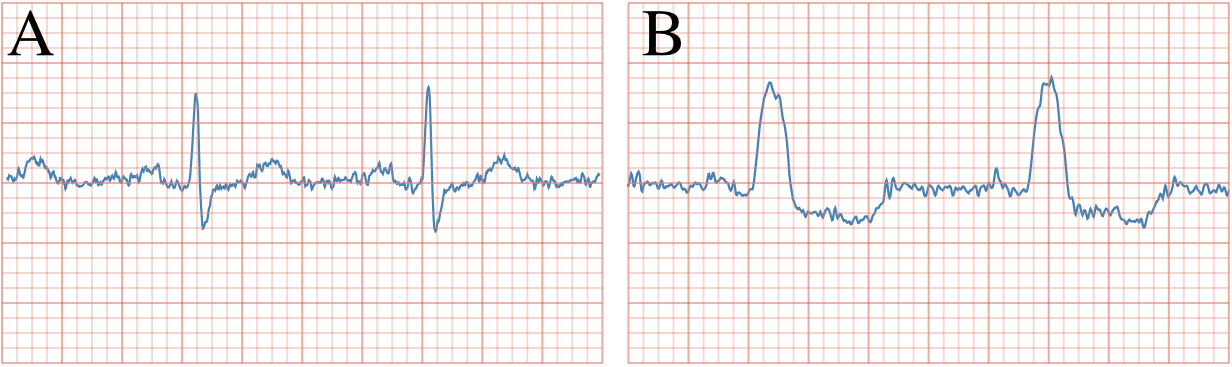

The advent of wearable devices incorporating electrocardiography (ECG) sensors has provided consumers the ability to detect signs of an abnormal heart rhythm. In this section, we demonstrate the utilisation of a small neural network architecture suitable for deployment, e.g. to a mobile device connected to such a biosensor, to be trained on ECG data from the the China Physiological Signal Challenge (CPSC) 2018 challenge dataset (Liu et al., 2018). We selected the task of automated Left Bundle Branch Block (LBBB) detection, formulated as a binary classification task against a normal (sinus) rhythm. This task is clinically relevant, as the sudden appearance of LBBB can herald acute coronary syndrome which requires urgent attention to avert myocardial infarction. As ECG data constitutes personal health information, its protection is mandated both legally and ethically. We utilised -DP-SGD for training a complex-valued neural network on Fourier-transformed ECG acquisitions. We adopt this strategy as it can benefit from two key properties of the Fourier transform: ECG data can contain high-frequency noise which is irrelevant for diagnosis and can be reduced using Fourier filtering. Concurrently, this technique compresses the signal, which can drastically reduce the amount of data transferred. Table 2 shows classification results and Figure 1 shows exemplary source data.